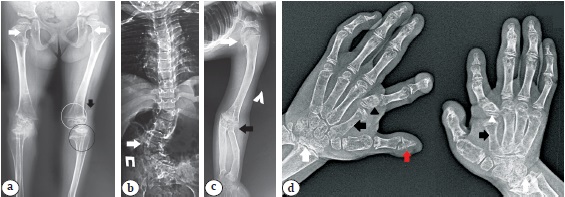

На рентгенограммах нижних конечностей в переднезадней проекции можно отметить следующие особенности: проксимальные отделы бедренных костей имели форму «гаечного ключа», малый вертел удлиненно-конусовидной формы; широкий и укороченный перешеек подвздошной кости, горизонтальное положение свода вертлужной впадины, гипоплазия эпифизов бедренных костей. Метафизы бедренных и большеберцовых костей укорочены и расширены. Умеренный сколиоз позвоночника выявлен на снимке грудопоясничного отдела позвоночника (рис. 5 b). На рентгенограммах кистей рук: опережение костного возраста (соответствует возрасту 5 лет), короткие пястные кости, широкие фаланги (преимущественно больших пальцев) (рис. 5 с).

Рис. 5. Пробанд 3 — мальчик, обследованный в возрасте 2 года 8 мес.:а — внешний вид — непропорционально низкий рост с относительно короткими конечностями, узкая грудная клетка, короткая шея, поясничный гиперлордоз, большой размер головы, округлое лицо, выпуклые глаза, вдавленная переносица, микрогнатия;b — рентгенограмма нижних конечностей и позвоночника в прямой проекции: проксимальный отдел бедра имеет форму «гаечного ключа» (белые стрелки), удлиненный и конусообразный малый вертел (черные стрелки); широкий и укороченный перешеек подвздошной кости (черные треугольники); умеренный сколиоз позвоночника (красная стрелка);с — рентгенограмма кистей рук: опережающий костный возраст, короткие пястные кости, широкие фаланги пальцев